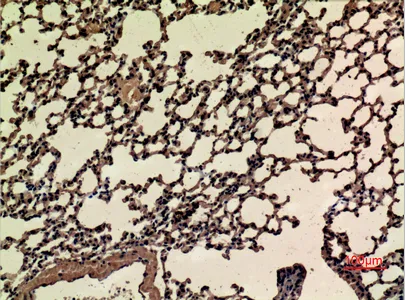

CD68 Rabbit Polyclonal Antibody

Cat: APRab08436

Size1:50μl Price1:$118

Size2:100μl Price2:$220

Size3:500μl Price3:$980